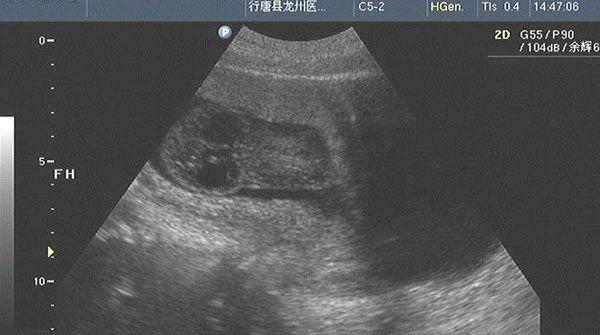

确诊患有淋巴水囊瘤的诊断报告

淋巴水囊瘤是属于先天性淋巴组织疾病,一般在胎儿时期就会出现,但是因为其症状往往较轻而容易被人忽视,等到症状明显时,常常表现出呼吸困难或者是食道压迫等症状。在nt检查的时间里,如果患有淋巴水囊瘤,则会导致nt值偏高,如果nt值能够达到7.2mm,那么胎儿患病的几率将会大幅度提高。